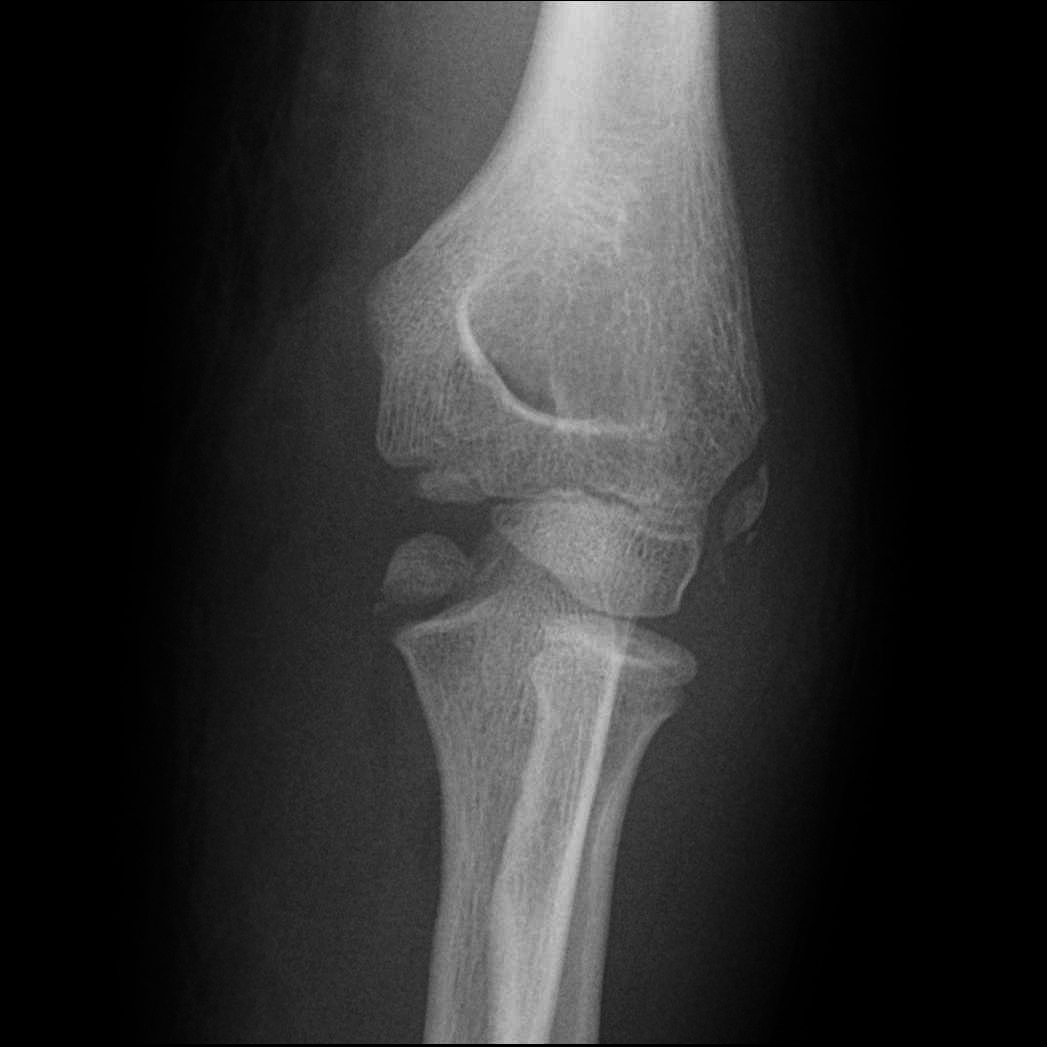

Welche wichtige, jedoch leicht zu übersehende Verletzung erkennen Sie auf diesem Ellenbogenröntgen eines 12-jährigen Patienten nach erfolgter Reposition einer vorangegangenen Ellenbogenluxation?